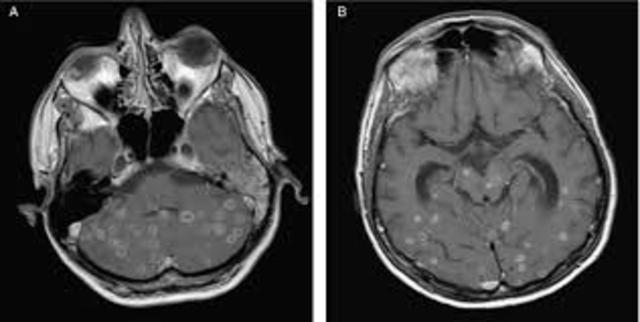

las lesiones se analizan con aspectos positivos y negativos